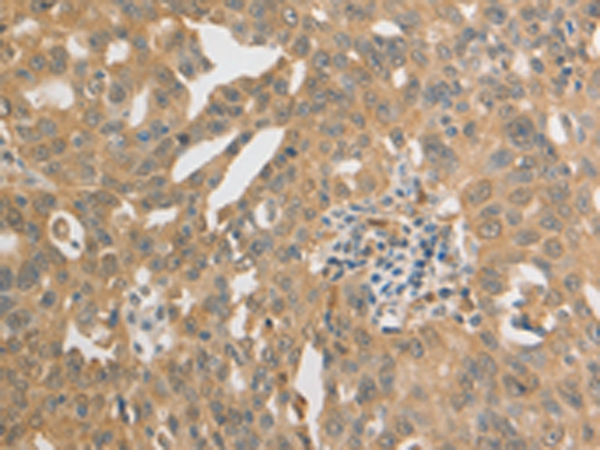

分类: 科研抗体货号: P11099别名: PRP; TSA; PRX2; PTX1; TPX1; NKEFB; PRXII; TDPX1; NKEF-B应用: WB,IHC反应种属: Human, Mouse, Rat

分类: 科研抗体货号: P11098别名: PAG, PAGA, PAGB, PRX1, PRXI, MSP23, NKEFA, TDPX2, NKEF-A应用: WB,IHC反应种属: Human, Mouse, Rat